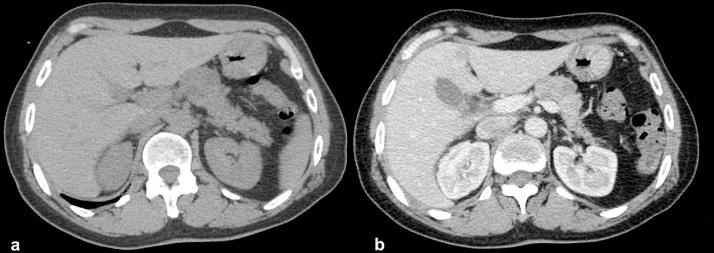

Solid serous cystadenoma is an uncommon benign pancreatic tumor, with only, including this case, 21 cases published so far. It is often misdiagnosis with other malignant pancreatic tumors. Below we report a new case of a solid serous cystadenoma of the pancreas treated by laparoscopic distal pancreatectomy in 53-year-old female who presented with epigastric pain. Histological and immunohistochemical examination revealed a solid serous cystadenoma of the pancreas. Preoperative diagnosis of this subtype of serous cystadenoma is difficult, and, due to its benign nature, conservative resection of the tumor is the recommended treatment. After analyzing the literature, including this case from our department, we discuss clinical presentation, imaging characteristics and histopathological findings, considering in particular difficulties in preoperative diagnosis, feasibility of laparoscopic resection.

实性浆液性囊腺瘤是一种罕见的胰腺良性肿瘤,迄今为止包括本病例在内仅有21例报道。它常被误诊为其他胰腺恶性肿瘤。以下我们报告一例53岁出现上腹部疼痛的女性胰腺实性浆液性囊腺瘤,经腹腔镜远端胰腺切除术治疗的新病例。组织学和免疫组化检查显示为胰腺实性浆液性囊腺瘤。这种浆液性囊腺瘤亚型的术前诊断困难,并且由于其良性性质,推荐对肿瘤进行保守性切除。在分析文献(包括我们科室的本病例)后,我们讨论了临床表现、影像学特征和组织病理学发现,尤其考虑了术前诊断的困难以及腹腔镜切除的可行性。